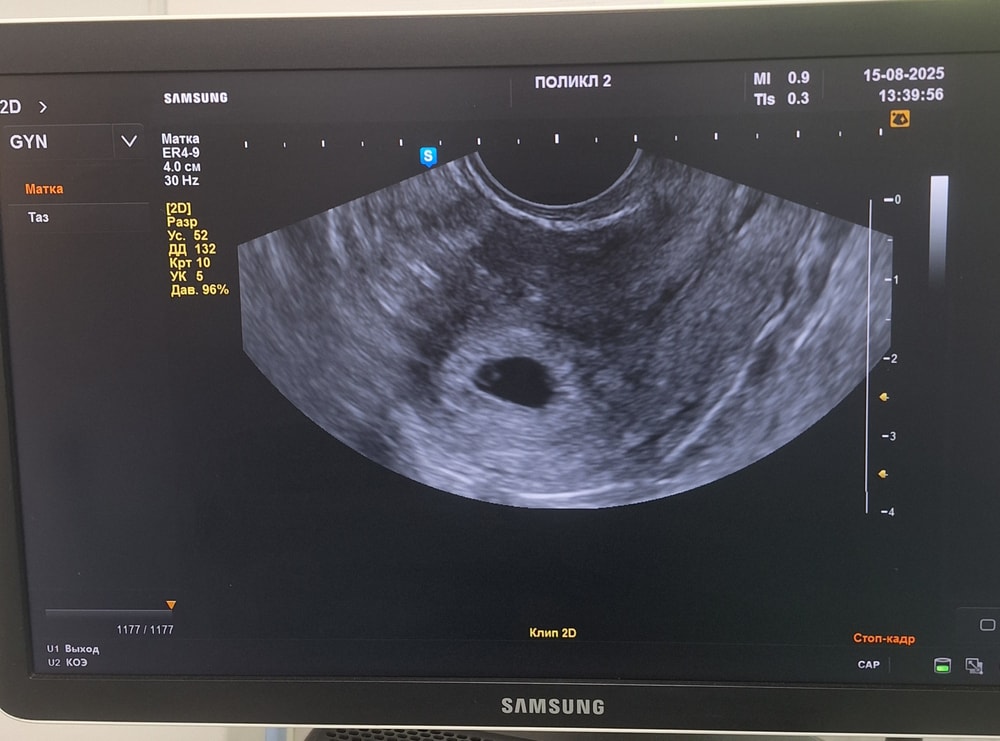

Сегодня 18 ДПП с утра было немного коричневой мазни, сделали трансвагинальное УЗИ и вот что увидели.

Врач говорит, белая точечка в ЖМ - это, скорее всего, и есть наш крошка. Гематом и отслоек не увидели. Как думаете, для 18 ДПП приличная картинка получается? 🤔

Юлия Ю, 5 н 1д сегодня, а по узи написали 5-6 недель.